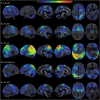

Figure 2. Regions of Gray Matter Loss in Patients With CBS According to Pathology Category

All results are FWE-corrected for multiple comparisons, p < 0.05, extent threshold = 20. Legends show t scores with brighter colors representing higher score. N = 103 (24 CBD, 13 AD, 11 PSP, 7 TDP43, 4 DLBD/AD, 4 other, 40 controls). AD = Alzheimer disease; CBD = corticobasal degeneration; CBS = corticobasal syndrome; D = dominant; DLBD = diffuse Lewy body dementia; FWE = family-wise error; ND = nondominant; PSP = progressive supranuclear palsy; TDP = TAR DNA-binding protein 43.